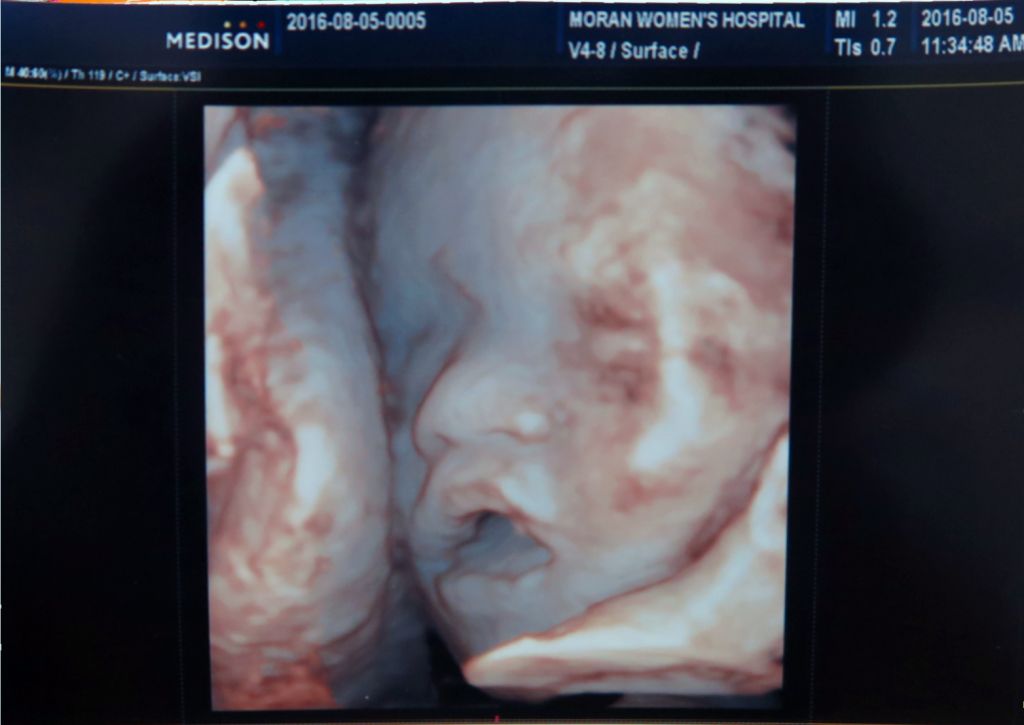

우리 가정에 기다리고 기다리던 새가족이 왔습니다^^ 2016년 10월 26일. 예정일을 지나서도 엄마 뱃속이 좋다며 나오지 않으려는 별이. 의사 선생님과 상담하여 유도분만을 시도하기로 한 날이되어 아침부터 병원으로 향했습니다. 촉진제를 맞고 얼마 되지 않아 진통이 시작되었습니다. 진통하는 동안 수시로 태동검사를 하더라구요. 진통과 분만에 도움이 된다하여 틈틈이 짐볼을 가지고 운동했어요. 부모와 할머니 할아버지들의Read More →